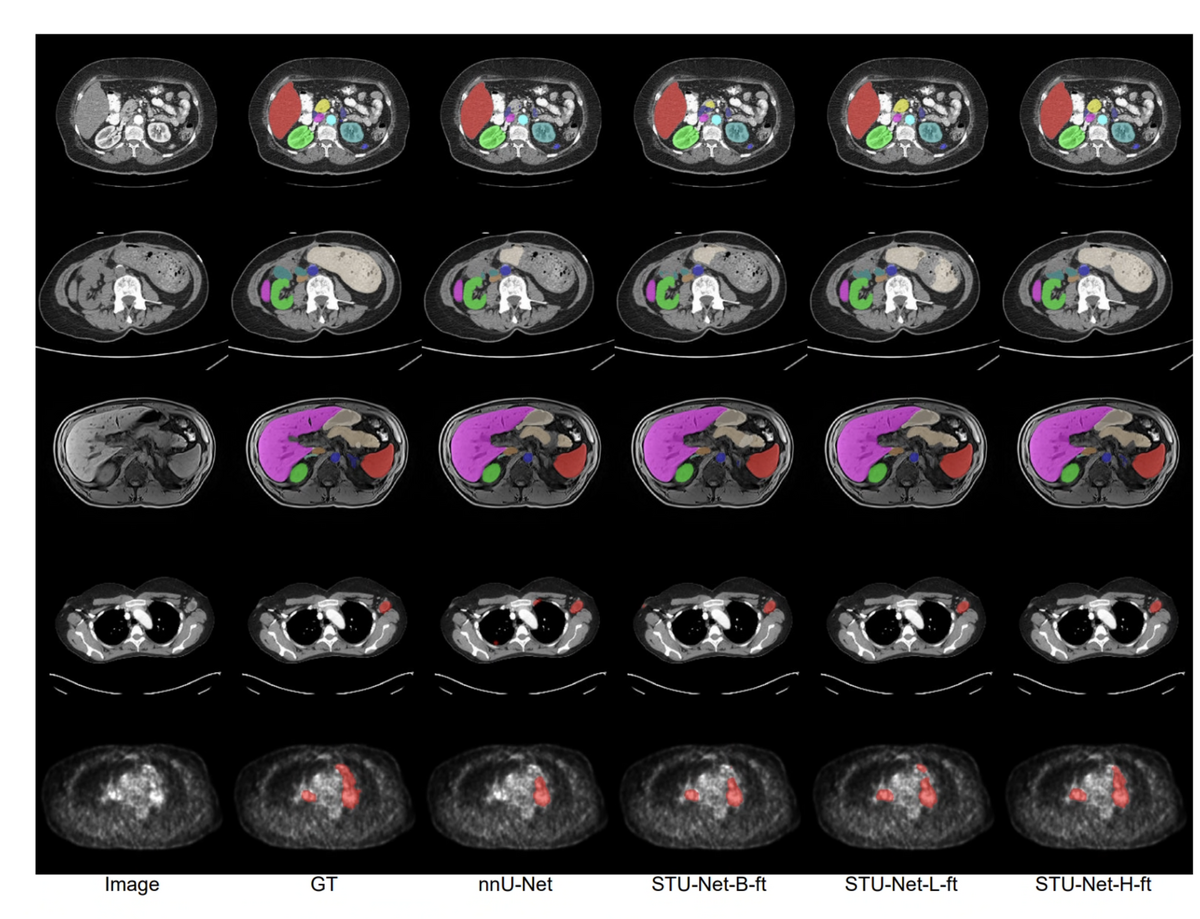

STU-Net qualitative CT segmentation results

Scaling Laws in Medicine: STU-Net from 14M to 1.4B Parameters

STU-Net segmentation results

STU-Net establishes scaling laws for 3D medical image segmentation. A family of four models — S (14M), B (58M), L (440M), and H (1.4B) — are pre-trained on TotalSegmentator (1,204 CT volumes, 104 anatomy classes). STU-Net-H achieves 90.06% mean DSC, surpassing nnU-Net by 3.3 points and all Transformer competitors. At 1.4B parameters, a single universal model outperforms five category-specific specialist models — a decisive step toward a medical segmentation foundation model.

STU-Net-H (1.4B) TotalSegmentator MICCAI 2023 Champion Transfer Learning